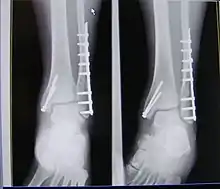

| X-ray of trimalleolar fracture repair before and after ORIF surgery | |

A trimalleolar fracture also known as Cotton fracture,[1] is a fracture of the ankle that involves the lateral malleolus, the medial malleolus, and the distal posterior aspect of the tibia, which can be termed the posterior malleolus. The trauma is sometimes accompanied by ligament damage and dislocation.[2]

Surgical repair using open reduction and internal fixation is generally required, and because there is no lateral restraint of the foot, the ankle cannot bear any weight while the bone knits. This typically takes six weeks in an otherwise healthy person, but can take as much as twelve weeks. Non-surgical treatment may sometimes be considered in cases where the patient has significant health problems or where the risk of surgery may be too great.[2]